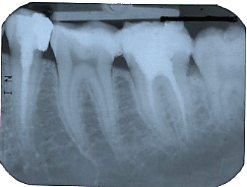

Es kann natürlich auch einmal nach einer Behandlung durch einen Zahnarzt röntgen nach 2 Wurzelbehandlungenzu Schmerzen in den Zähnen kommen, vor allem wenn Löcher in den Zähnen schon tief sind und fast bis zum Zahnnerv reichen. Aufgrund seiner Ausbildung und Erfahrung kann der Zahnarzt aber dieses Risiko viel besser abschätzen und den Patienten lange schmerzvolle Stunden ersparen. - Ganz abgesehen von der Tatsache, daß Behandlungen die nicht von Zahnärzten durchgeführt werden gegen das Gesetz verstoßen.